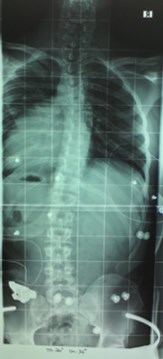

Das Röntgenbild vom November 2011 ist etwa 6 Wochen nach der Kur in Bad Salzungen geschossen worden. Mit 26° thorakal war das mein bester Wert, den ich je hatte. Leider bin ich dann wieder auf das Anfangsniveau von 34° thorakal zurück gefallen, trotz Korsett von cctec und ca. 120 Minuten Schroth-KG pro Woche. Ich muss dazu noch sagen, dass ich von Oktober 2010 bis November 2011 ein Korsett von Rahmouni getragen habe, allerdings nur etwa 8 Stunden am Tag, und die auch nicht am Stück. Das Korsett von cctec habe ich im Schnitt auch nur 8-10 Stunden pro Tag getragen. Aus privaten Gründen trage ich es seit Dezember 2013 nur noch sehr unregelmäßig, manchmal 3 Tage am Stück gar nicht, dann wieder 8 Stunden.

Röntgenbilder vom November 2011 und August 2013 bei Dr. Wilke

Vergleich 11-11 und 08-13 anonym.jpg (29.08 KiB) 9750 mal betrachtet